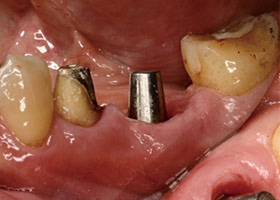

拔牙當天立即植體植入,傷口縫合